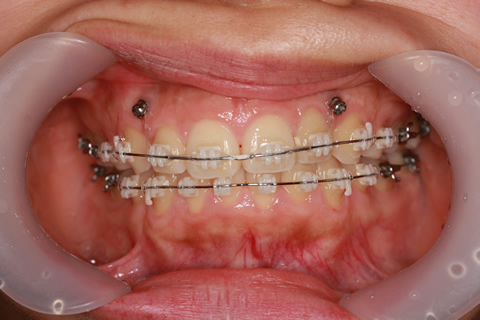

症例7(歯肉形成を併用した矯正治療)

治療前

歯肉形成(形成)症例7(歯肉形成を併用した矯正治療No.2)治療前

治療中

治療後

歯肉形成(形成)症例7(歯肉形成を併用した矯正治療No.2)治療後

年齢・性別

16歳

治療期間

3年6ヶ月

抜歯

なし

治療費

80万円

備考

治療内容

噛み合わせが深いのを改善するために前歯上歯肉に2本のスクリューを埋入して牽引。

施術の副作用(リスク)

疼痛、咬合時痛、知覚過敏、歯根吸収、歯肉退縮が生じる可能性があります。